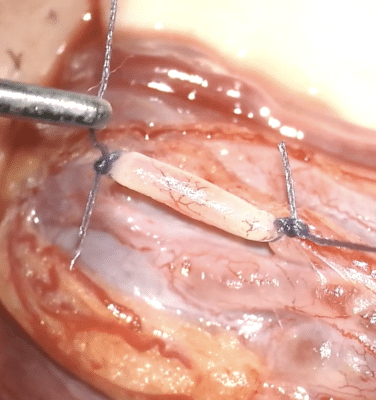

Aktualitások a herevisszér kivizsgálásában és kezelésében

A varicocele – magyarul herevisszér – a férfi meddőség egyik leggyakoribb, de jól kezelhető oka. Lényege, hogy a here körüli vénák kitágulnak, a pangó vér miatt megemelkedik a here hőmérséklete, fokozódik az oxidatív stressz, és romlik a spermiumtermelés. Bár sok férfinél tünetmentes, másoknál herefájdalommal, húzó érzéssel járhat, és gyakran csak meddőségi kivizsgáláskor derül ki.

A 2025-ös kutatások szerint a varicocele hátterében nem csupán mechanikai okok állnak, hanem genetikai és molekuláris tényezők is. A diagnosztika fejlődött: új képalkotó módszerek és laborvizsgálatok (például a spermium DNS-fragmentációja) segítik megítélni a betegség súlyosságát. Kezelés akkor szükséges, ha rossz spermakép, meddőség, fájdalom vagy serdülőkori fejlődési elmaradás jelentkezik. A mikrosebészeti műtét továbbra is a leghatékonyabb, de egyre elterjedtebbek a minimálisan invazív, radiológiai megoldások is. A jövő célja a személyre szabott terápia, amely felesleges műtétek elkerülésével, célzott beavatkozásokkal javítja a férfiak termékenységét – írta összefoglalójában dr. Takács Tamás.

Recent Trends in the Management of Varicocele

J. Clin. Med. 2025, 14(15), 5445. https://doi.org/10.3390/jcm14155445